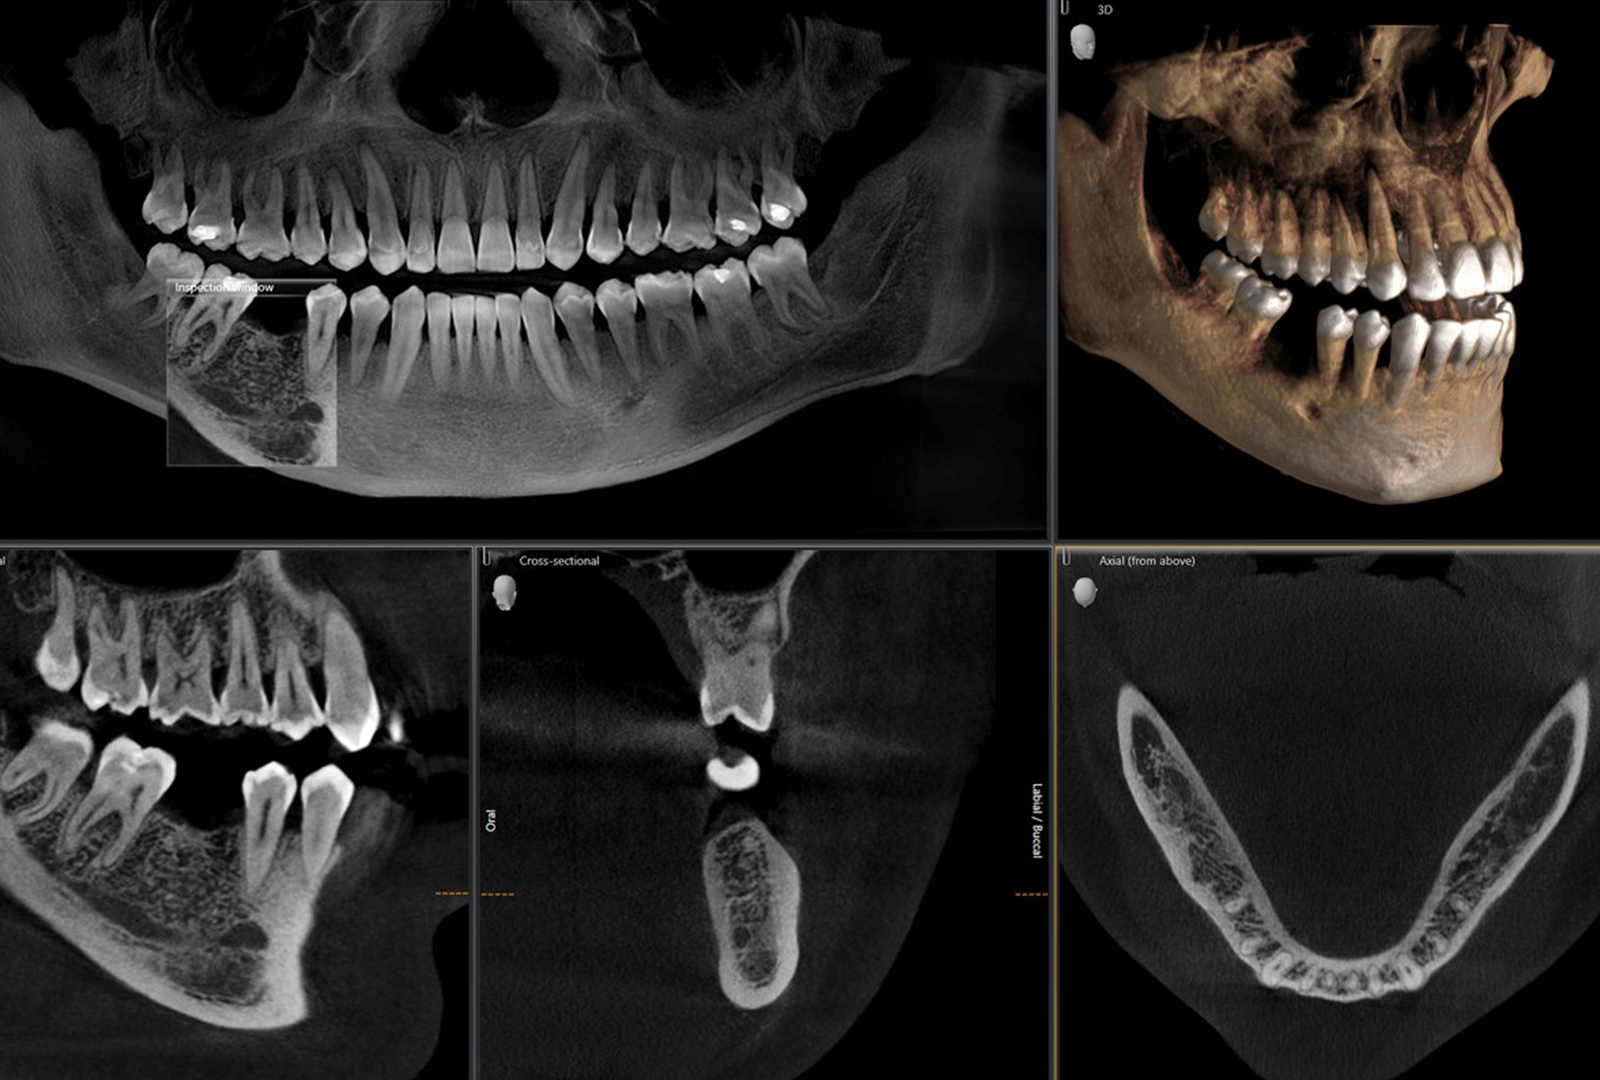

This course concentrates on digital workflow technology principles, ranging from diagnostics and CBCT imaging to how to transfer patient photography to digital design software. Participants will learn how to design, manufacture, and scan crowns and bridges using CAD/CAM technology.

This course gives clinicians insight into restorative and periodontal treatment diagnostic techniques. Participants will learn to produce digital and analog impressions and interpret radiographs and CBCT scans to determine the pulpal status of the teeth for proper tissue management.